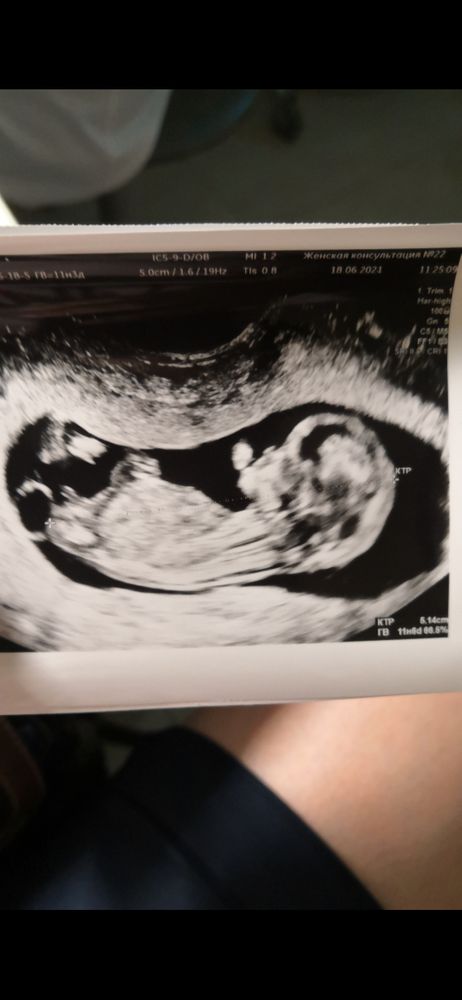

Бугорок половой

Если это половой бугорок и я его ни с чем не путаю, то, думаю, мальчик. У сына примерно под таким же углом торчал бугорок, у дочки лежал параллельно. Но, возможно, у всех по-разному.

Мне кажется мальчик, но я не профи - могу ошибиться, так как ракурс неудачный

Фото так себе, конечно... Если правильно вижу половой бугорок, то он девчачий. А так, не точно из-за качества фото.

Если это действительно бугорок, то девчуля 😁

Бугорка не видно, ребёнок спинкой повернут, у нас так тоже было

Настя Литвинова, тогда бы ракурс личика было видно (есть ещё способ по лбу определяют 🙈🤭) , как по мне ребёнок лежит на одной ягодице полу спинкой да и вроде как позвоночник видно (чёрная линия вдоль спинки…) но если то что похоже на бугорок он и есть, то я бы сказала по нему что девчонка🎀 Вы извините, но Ваш пост я перенесу в дневник, не та тематика для сообщества зачатие. Можете попробовать продублировать его в одном из сообществ о Б.

Очень не четкую конечно вам фоточку дали😅По ней вообще сложно понять,где что,не то что половой бугорок🤔

На фото бугарка не видно(

Настя Литвинова, это часть ножки